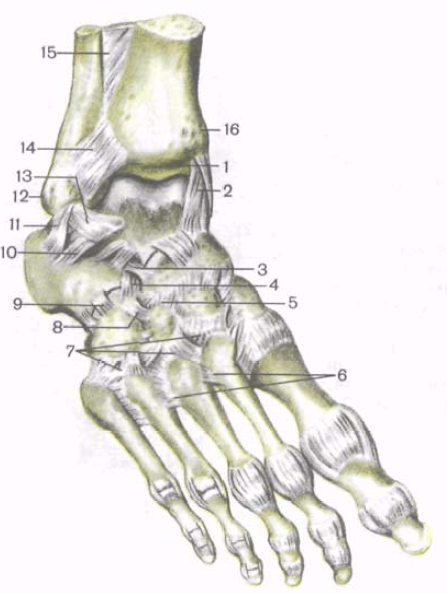

Анатомия суставов Шапарова и Лисфранка: фото и информация